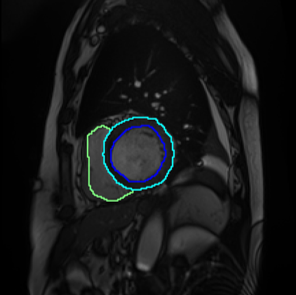

Figure 1: Different sections of a heart. (a) represents the basal section, which lacks regions of the right ventricle(RV), myocardium, and the left ventricle(LV); (b), (c), and (d) approach the apical section, while the RV, myocardium, and LV vary in size and shape.

French et al.[13] emphasized that consistency regularisation requires robust and diverse perturbations in semantic segmentation, which leads networks to possess a strong ability to generalize. Perturbations are usually performed using a set of data augmentation algorithms, and consistency regularization uses highly augmented images to efficiently learn unlabelled data. In terms of the intricate anatomical shapes in greyscale medical images, data augmentation algorithms should be able to enable the segmentation model to identify the shapes of objects, especially contours. Furthermore, medical images sometimes do not contain objects from some specific classes, which can lead to inter-class imbalance (Figure 1). To address these challenges, we introduce Scaling-up Mix with Multi-Class (SM22{}^{2}start_FLOATSUPERSCRIPT 2 end_FLOATSUPERSCRIPTC), a novel data augmentation algorithm based on image mixing techniques to generate a more diversified training dataset. Targeting the primary tasks of semantic segmentation - region and contour recognition - our algorithm processes the shapes of segmentation objects and merges semantic features from multiple original images into a novel composition. We incorporate the method into a pseudo-labeling framework to improve the teacher model’s ability to learn unlabeled data and conduct experiments on three medical image datasets.